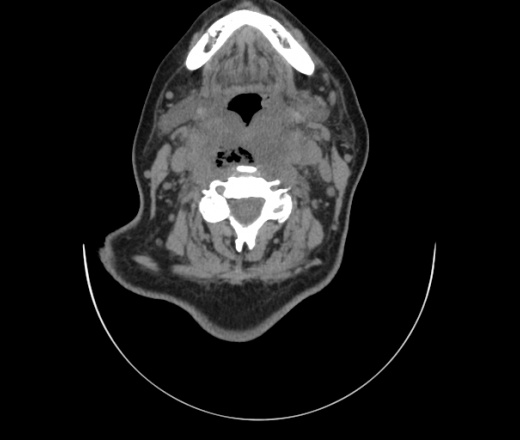

Женщина поступила в х/о спустя 4 дня после того как при употреблении карася подавилась костью.

Наличие газа в средостении на протяжении тел С2-С6 (медиастинальна эмфизема); рыбная кость на уровне тела С6.

При всем уважении, но говорить о медиастинальной эмфиземе, оценивая мягкие ткани шеи, как-то слишком резко. На мой взгляд, это ретрофарингеальное пространство.

Эвакуировали почти 100мл гноя. Но кость не смогли найти. Думаю что она даст дальнейшее ослоднение. Эндоскопически за черпалонадгортаной звязкой не смогли зайти в пищевод, все мягкие ткани отечные, просвет пищевода сдавлен. По всей видимости параэзофагеальная клетчака тоже задействована. Эмпиема, если ее можно так назвать, незнаю как правильно дошла до уровня яремной вырезки. Чем закончиться напишу. Ждем медиастинита.

Флегмона заглоточного пространства шеи, только операция, флегмоны вскрывают. Риск медиастинита.

Согласен с Вами; конечно, наличие газа в клетчатке ретрофарингеального пространства (затмение с опечаткой..). К сожалению, процесс "продвигается" к медиастиниту. Но почему никто, не отмечает наличие рыб. кости; или это для Всех очевидно?

Так вы уже отметили. Хотя ориентировал бы не скелетотопически, а на перстнечерпаловидный сустав.

Кость то мы сразу выявили, размеры где то 17*2мм, но ее так и не получается найти в этой каше